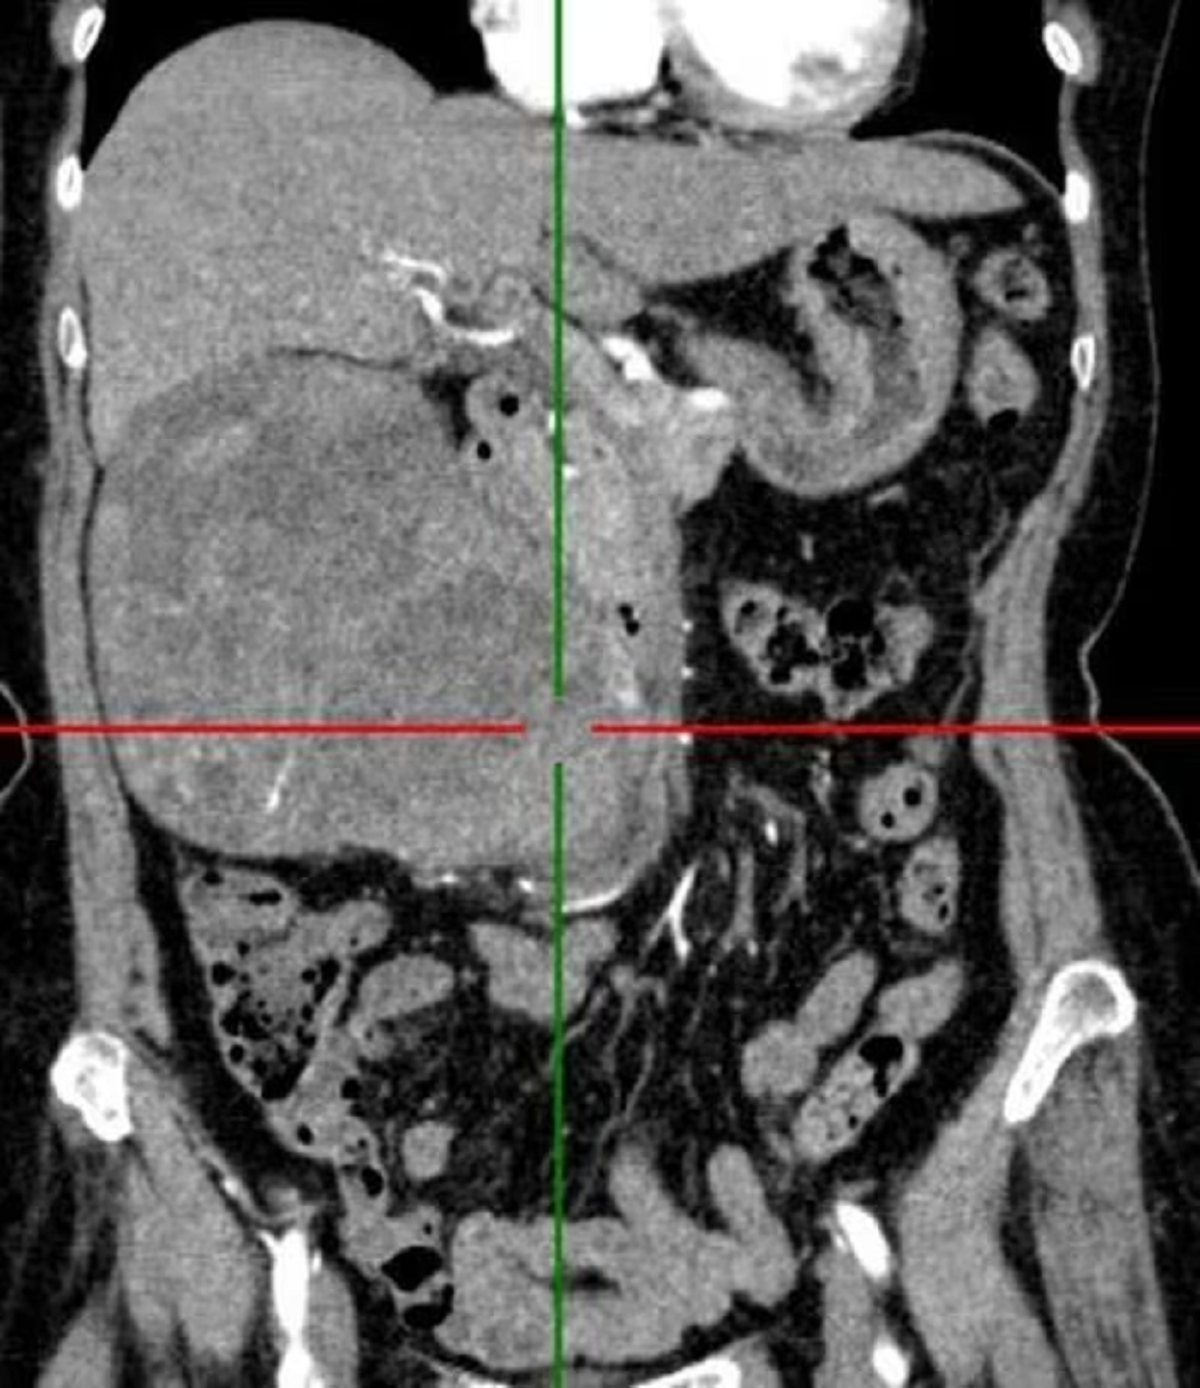

Khai thác tiền sử bệnh cụ bà 72 tuổi nhập viện vì đau âm ỉ vùng hông lưng phải kéo nhiều tháng nay. Sau khi thăm khám và làm xét nghiệm các bác sĩ kết luận nữ bệnh nhân u thận phải.

Tại viện sau hội chẩn khoa, ê-kíp đã quyết định can thiệp phẫu thuật phù hợp, loại bỏ hoàn toàn khối u cho người bệnh. Các bác sĩ Khoa Ngoại thận - Tiết niệu và Nam học, Bệnh viện đa khoa tỉnh Tuyên Quang đã cắt bỏ khối lượng u to, trọng lượng 1,2kg cho bệnh nhân.